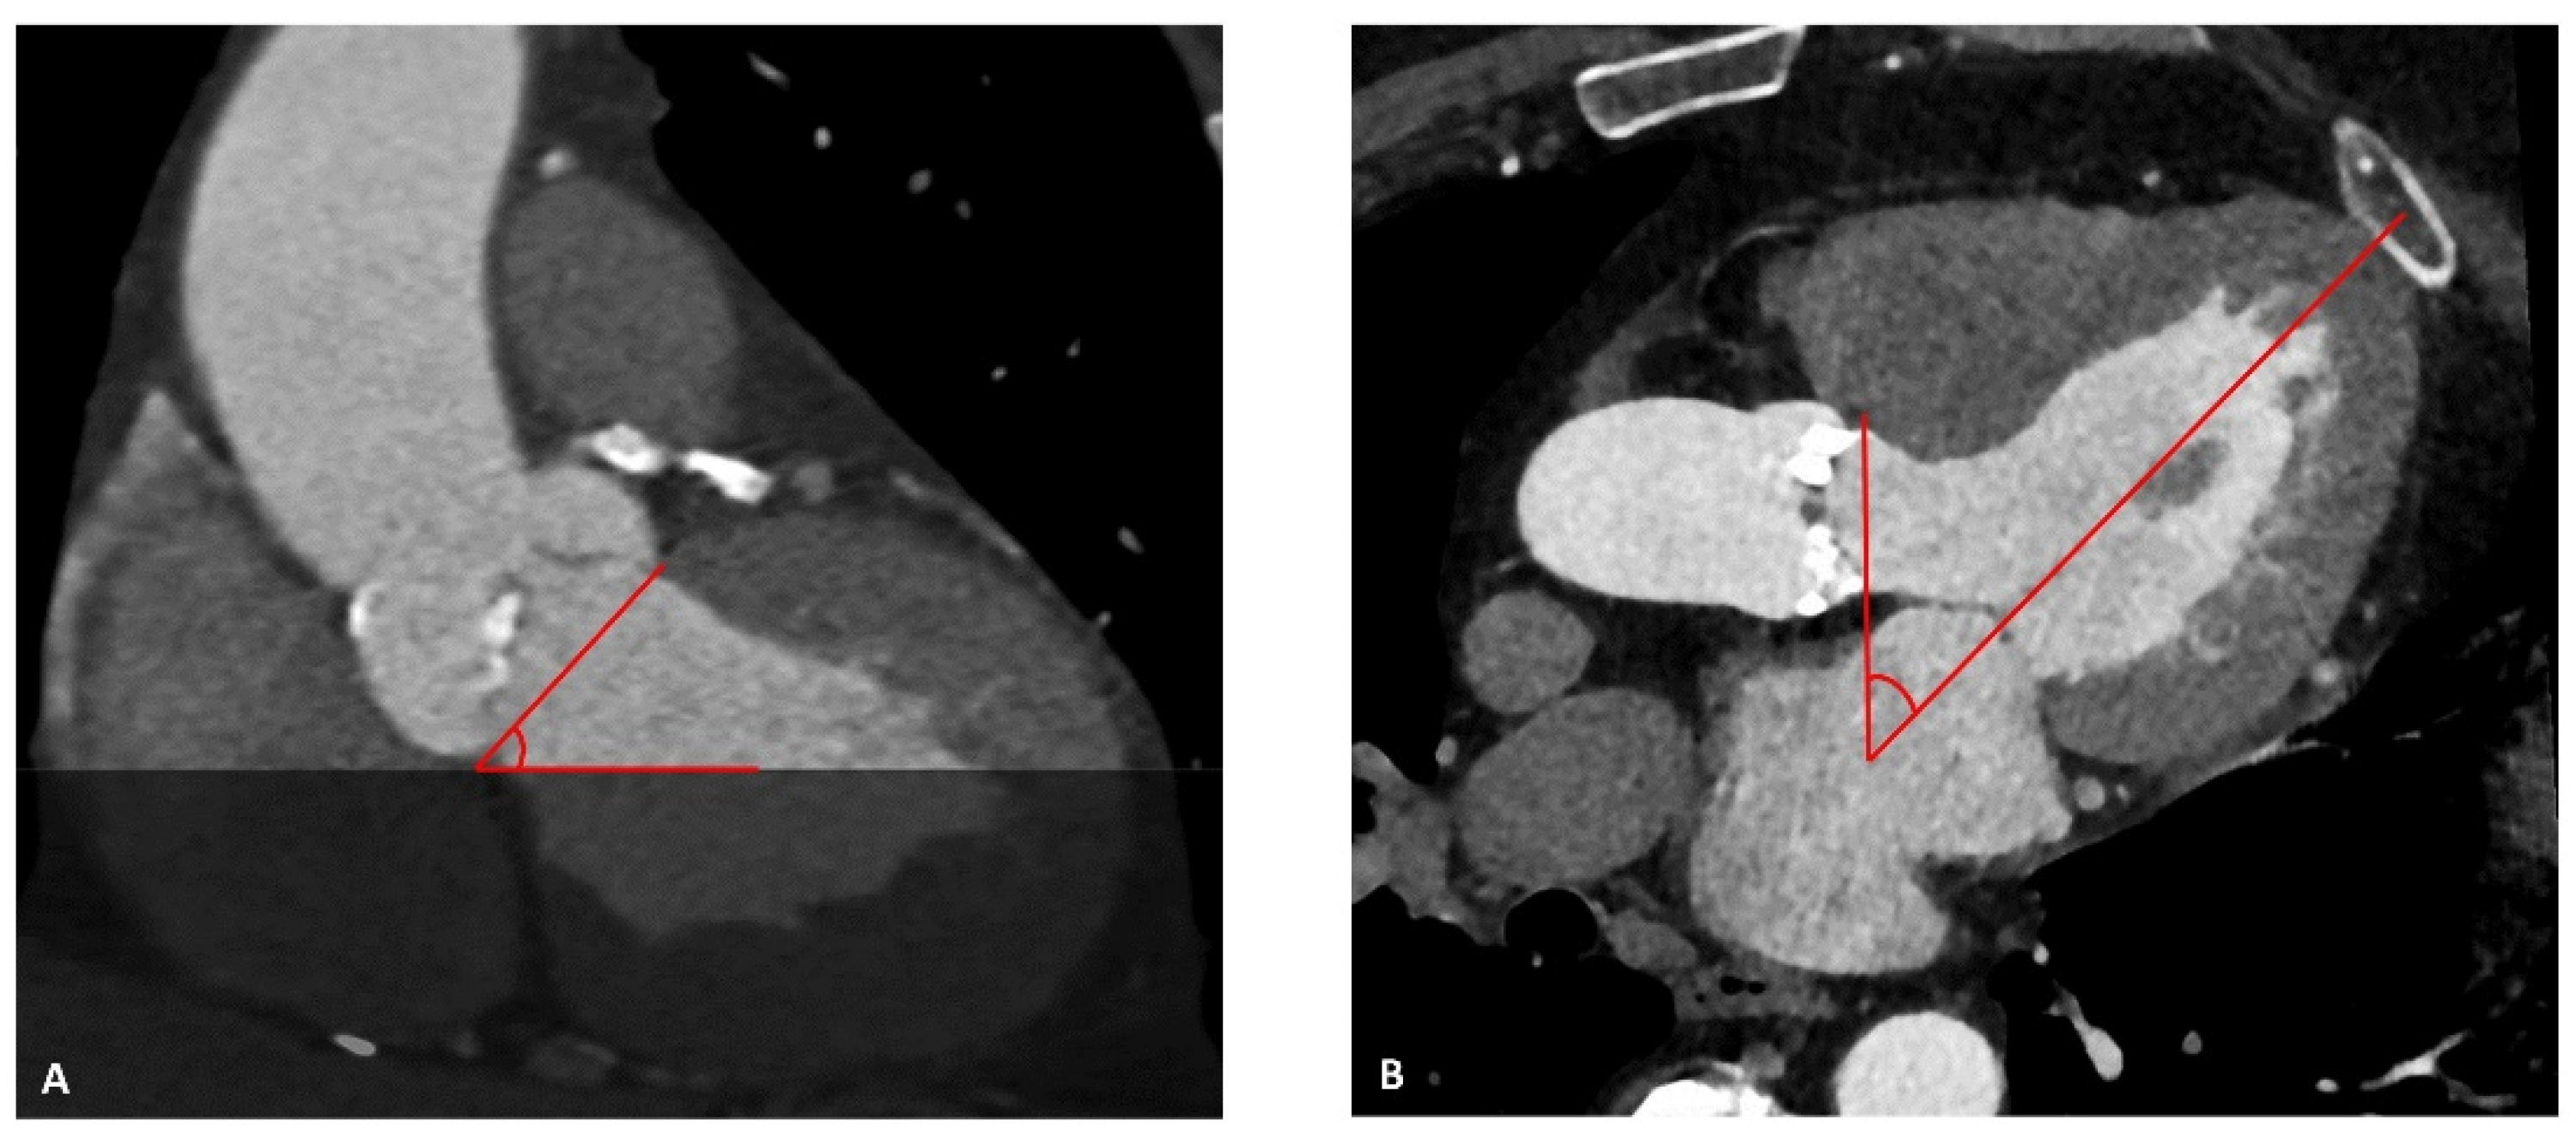

2.4. Assessment of Aortic Geometry